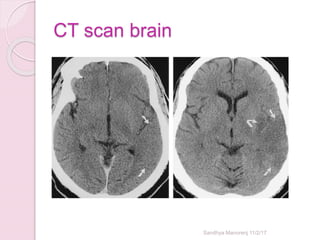

CT scan brain

Sandhya Manorenj 11/2/17

• #36 SDH,EDH,Brain mets. subdural hematomas are classically crescent-shaped, with a concave surface away from the skull. However, they can have a convex appearance, especially in the early stage of bleeding.